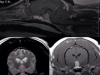

МРТ головного мозга для животных используют для определения следующих расстройств: гидроцефалии, воспалительных заболеваний, опухолей, кровоизлияний, анатомических мальформаций. Зачастую собакам и кошкам проводят МРТ-исследование головы и опорно-двигательного аппарата, но оно также доступно для изучения сердца, легких, печени, почек, щитовидки, надпочечников.

Спинной мозг и позвоночный канал применяют в целях обнаружения экструзий и протрузий межпозвонковых дисков, спондилитов, миелитов, новообразований, некомпрессионных повреждений центральной нервной системы позвоночника.

Обследование для суставов и мягких тканей назначают, чтобы исключить синовиты, разрывы капсул сустава, а также для оценки роста опухолевого развития.